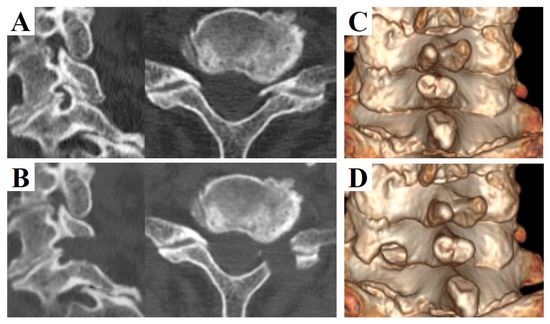

2.2. Operative Technique